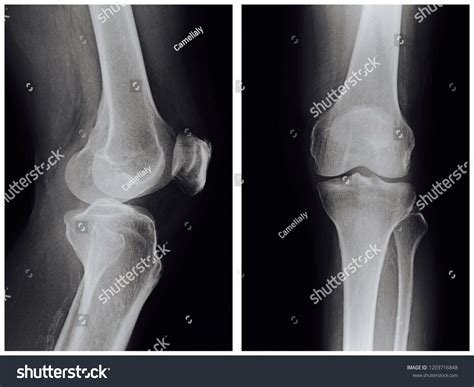

When experiencing persistent joint pain or following a traumatic injury, medical professionals often order specific diagnostic imaging to visualize the complex anatomy of the human leg. Among the most common and essential examinations is the Lateral Knee Xray. This specific projection is critical for clinicians to view the knee joint from the side, allowing for a precise evaluation of the patella, the joint space, and the relationship between the femur and the tibia. Understanding why this procedure is performed and how it contributes to an accurate diagnosis can help patients feel more prepared and informed during their medical journey.

The knee is a complex weight-bearing joint subjected to immense stress during daily activities. While an anteroposterior (AP) view provides a front-on perspective, the Lateral Knee Xray offers a vital profile view that cannot be captured from other angles. By isolating the joint from the side, radiologists and orthopedic surgeons can identify structural abnormalities that might be obscured in other views.

The primary goal of this imaging technique is to clearly delineate the bony structures of the knee. Because the soft tissues can sometimes overlap or obscure these bones, specific positioning is required to ensure that the femoral condyles are perfectly superimposed. When performed correctly, the Lateral Knee Xray highlights several key anatomical markers:

Anatomical Structure Clinical Importance in Lateral View

Patella Evaluates for vertical fractures or maltracking.

Femoral Condyles Superimposition indicates correct lateral positioning.

Tibial Plateau Assesses for depression fractures or bone spurs.

Joint Space Reveals loss of cartilage or signs of inflammatory arthritis.

Once the Lateral Knee Xray is captured, a radiologist examines the images for specific patterns of injury or disease. One significant sign looked for in cases of trauma is a "suprapatellar effusion." If a fracture is present, fat from the bone marrow may leak into the joint space, creating a distinct line on the X-ray that indicates internal bleeding. This is a classic indicator that requires immediate orthopedic consultation.